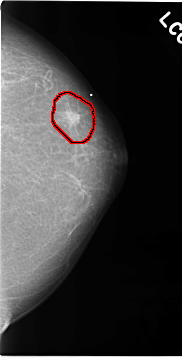

C_0118_1.LEFT_MLO

C_0118_1.LEFT_CC

FILE: C_0118_1.LEFT_CC.OVERLAY

TOTAL_ABNORMALITIES 1

ABNORMALITY 1

LESION_TYPE MASS SHAPE IRREGULAR MARGINS SPICULATED

ASSESSMENT 5

SUBTLETY 5

PATHOLOGY MALIGNANT

TOTAL_OUTLINES 1

BOUNDARY